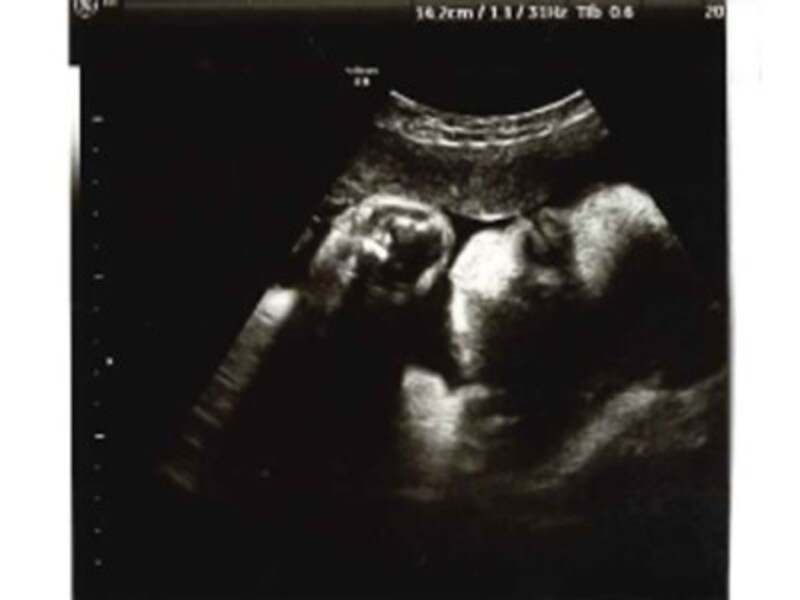

妊娠34週3日 (34w3d)の超音波 (エコー)写真 写真34w3dakotaさんg あなたのエコー写真も投稿してみませんか!妊娠34週0日 6mm 2156g 1776g 妊娠週数ごとの胎児と母親の状態の目安を一覧表にまとめました。 妊娠後期も葉酸が大切! 厚生労働省の指針では妊娠中は1日480μg摂取することが望ましいと言われいます。 これって茹でたほうれん草に換算すると4束くらいに相当します。 そんなに毎日食べるの厳しすぎますよね。 。 。 てか無理。 そんなときはサプリに頼っちゃいましょう! たくさんのサプリが販売されていますがおすすめは「 BABY葉酸~ママのめぐみ~ 」

妊娠34週目 34w0d 6d のエコー写真とエピソード 妊娠9ヶ月 Cozre コズレ 子育てマガジン